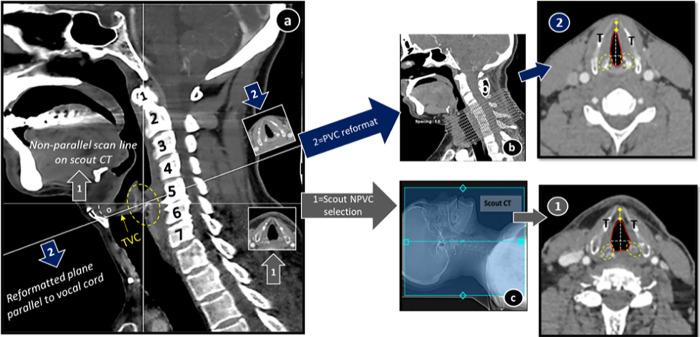

Oblique orientation of vocal cord demands strict compliance, by technicians and clinicians, to the recommended parallel plane CT scan of larynx. Repercussions of non-compliance has never been investigated before. We aimed to observe influence of non-parallel vocal cord plane CT scan on qualitative and quantitative glottic parameters, keeping parallel plane CT as a standard for comparison. Simultaneous identification of potential suboptimal imaging sequelae as a result of unformatted CT plane was also identified. In this study we included 95 normal adult glottides and retrospectively analyzed their anatomy in two axial planes, non-parallel plane ① and parallel to vocal cord plane ②. Qualitative (shape, structures at glottic level) and quantitative (anterior commissure ACom, vocal cord width VCw, anteroposterior AP, transverse Tr, cross-sectional area CSA) glottic variables were recorded. Multivariate statistical analysis was used to predict pattern and their impact on glottic anatomy. Plane ① displayed supraglottic features in glottis; adipose (90.5%) and split thyroid laminae (70.6%). Other categorical variables: atypical shape, submental structures and multilevel vertebral crossing were also in majority. All glottic dimensions varied significantly between two planes with most in ACom (-5.8mm) and CSA (-15.0 mm2). In contrast, plane ② manifested higher VCw (>73%), Tr (66.3%), CSA (64.2%) and AP (44.2%) measurements. On correlation analysis, variation in ACom, CSA, Tr was positively associated with VC or plane obliquity (p<0.05). This variability was more in obese and short necked subjects. Change in one parameter also modified other significantly i.e., ACom versus AP and CSA versus Tr. Results indicated statistically significant change in subjective and objective anatomical parameters of glottis on non-application of appropriate CT larynx protocol for image analysis hence highlighting importance of image reformation.

声带的斜位要求技术人员和临床医生严格遵守推荐的喉平行层面 CT 扫描。以前从未研究过不遵守规定的后果。我们旨在观察非平行声带层面 CT 扫描对定性和定量声门参数的影响,以平行层面 CT 扫描作为比较标准。同时还观察了由于 CT 层面未格式化而导致潜在的次优成像后遗症。在这项研究中,我们纳入了 95 例正常成人声门,并在两个轴面(非平行层面 ① 和与声带平行的层面 ②)中对其解剖结构进行了回顾性分析。记录了定性(形状、声门水平的结构)和定量(前连合 ACom、声带宽度 VCw、前后径 AP、横径 Tr、横截面积 CSA)声门变量。使用多变量统计分析来预测模式及其对声门解剖结构的影响。层面 ① 在声门中显示出了会厌结构;脂肪(90.5%)和甲状腺分裂的翼板(70.6%)。其他分类变量:非典型形状、颏下结构和多节段椎体交叉也占多数。两个层面之间所有声门参数均存在显著差异,其中 ACom 变化最大(-5.8mm)和 CSA(-15.0mm2)。相比之下,层面 ② 显示出较高的 VCw(>73%)、Tr(66.3%)、CSA(64.2%)和 AP(44.2%)测量值。在相关性分析中,ACom、CSA、Tr 的变化与 VC 或平面倾斜度呈正相关(p<0.05)。这种变化在肥胖和颈短的患者中更为明显。一个参数的变化也会显著改变其他参数,即 ACom 与 AP 和 CSA 与 Tr。结果表明,在不应用适当的 CT 喉部分析协议进行图像分析的情况下,声门的主观和客观解剖参数会发生统计学上的显著变化,因此突出了图像重构的重要性。